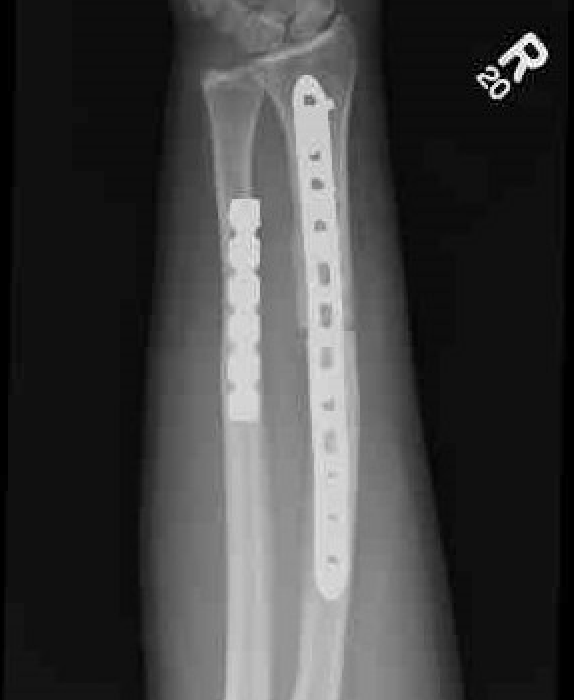

Radial malunion / Non anatomical ORIF of BBFF

Radial malunion after ORIF of BBFF

Etiology

Non operative management of BBFF

Non anatomical ORIF of BBFF

Bone loss radius

Radius short

Lengthening radius difficult

Ulna shortening

Radius angulated / rotated

Radial osteotomy

TFCC repair +/- TFCC reconstruction